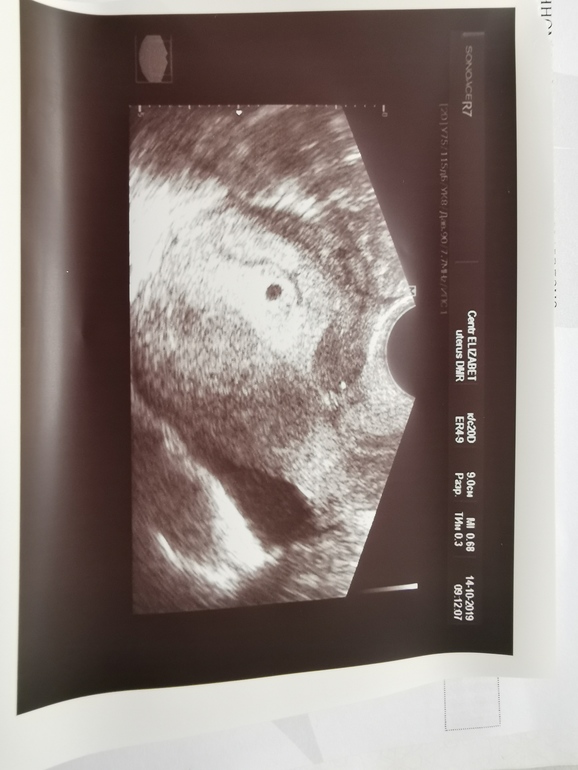

Сегодня сходила на узи, чтобы исключить вм.Вот результаты :

Эндометрий толщиной 19мм,децидуальный,полость матки расширена до 2 мм за счёт гипоэхогенного содержимого. В ср/3 полости матки плодное яйцо d3, 6 мм, желточный мешок визуализируется.Шейка матки правильной формы, контуры чёткие, ровные, структура мышечного слоя однородная,цервикальный канал не расширен.

Заключение беременность малого срока.